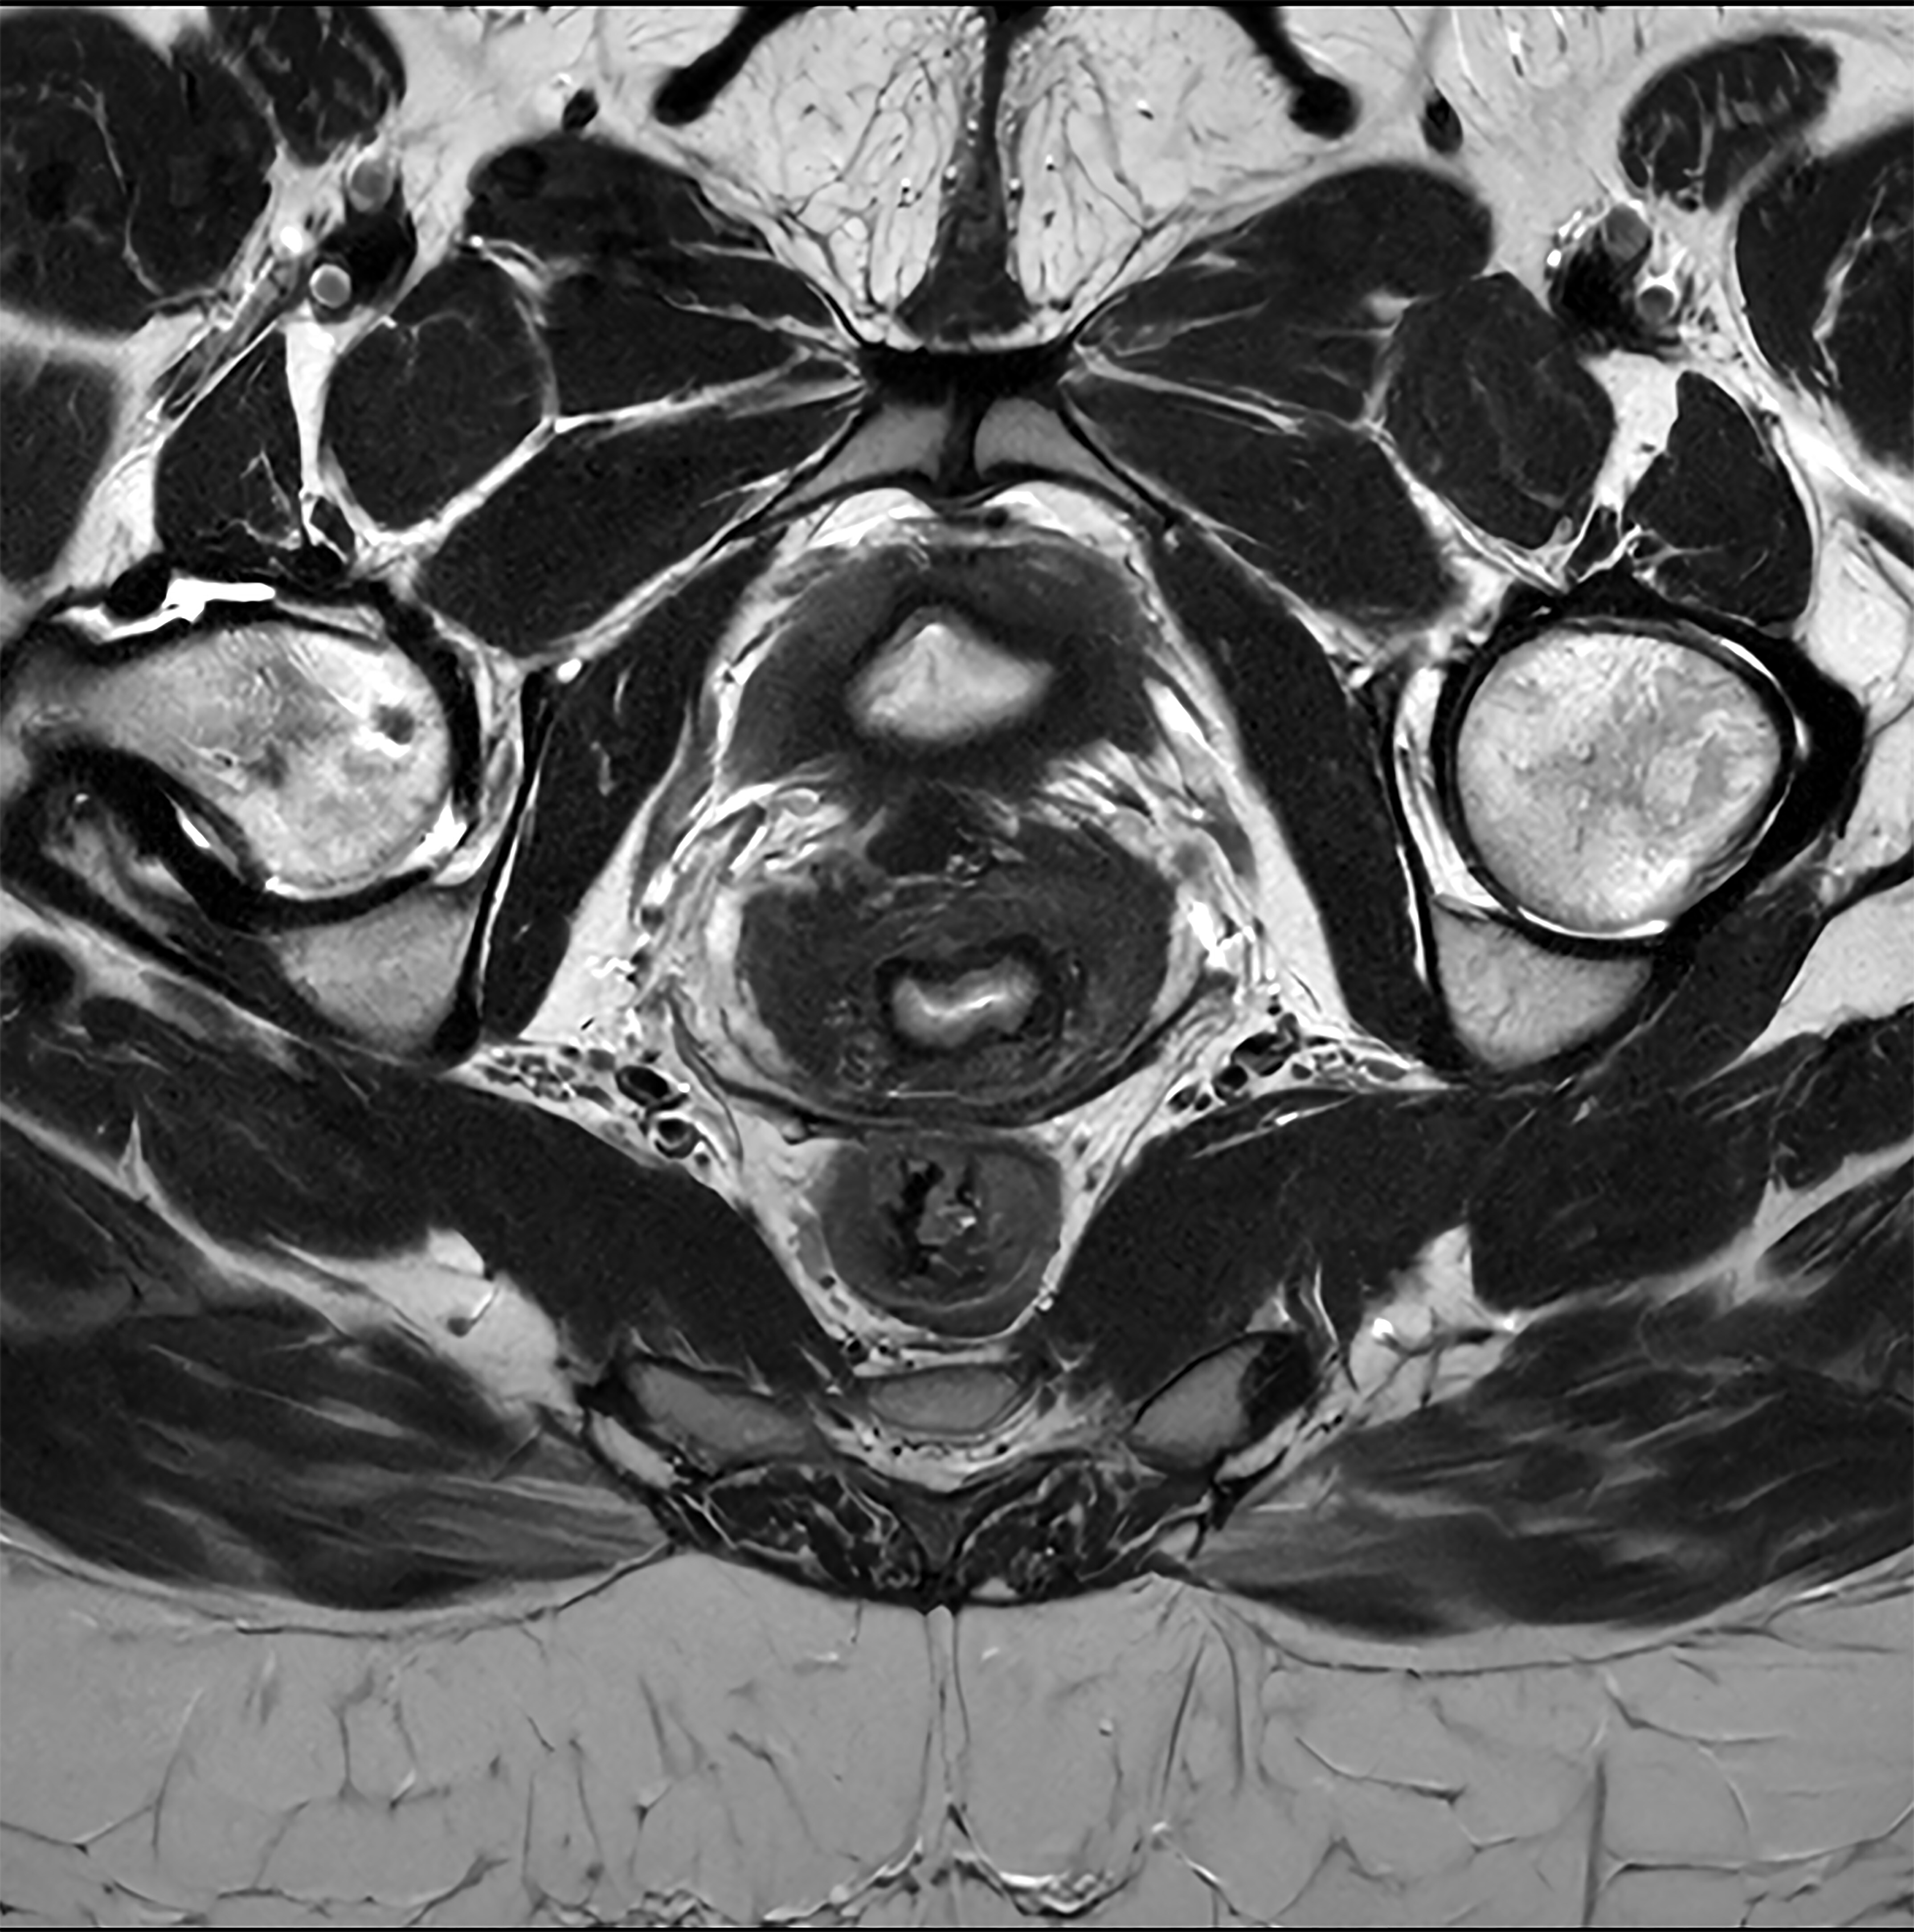

IVIM sequences can measure properties such as cellularity, perfusion, and vascular fraction, yielding qualitative and quantitative data. Images courtesy of Dr. Luis Martí-Bonmatí, PhD."Apparent diffusion coefficient (ADC) is simple and widely used but it is a bad matrix which introduces errors, due to the difference between centers and machines. ADC should be replaced with the IVIM matrix," Martí-Bonmatí said.

At today's session, ECR delegates will also learn how DWI state-of-the-art sequences can be standardized and optimized in clinical practice by using techniques like IVIM sequences to measure properties such as cellularity, perfusion, and vascular fraction, yielding qualitative and quantitative data.